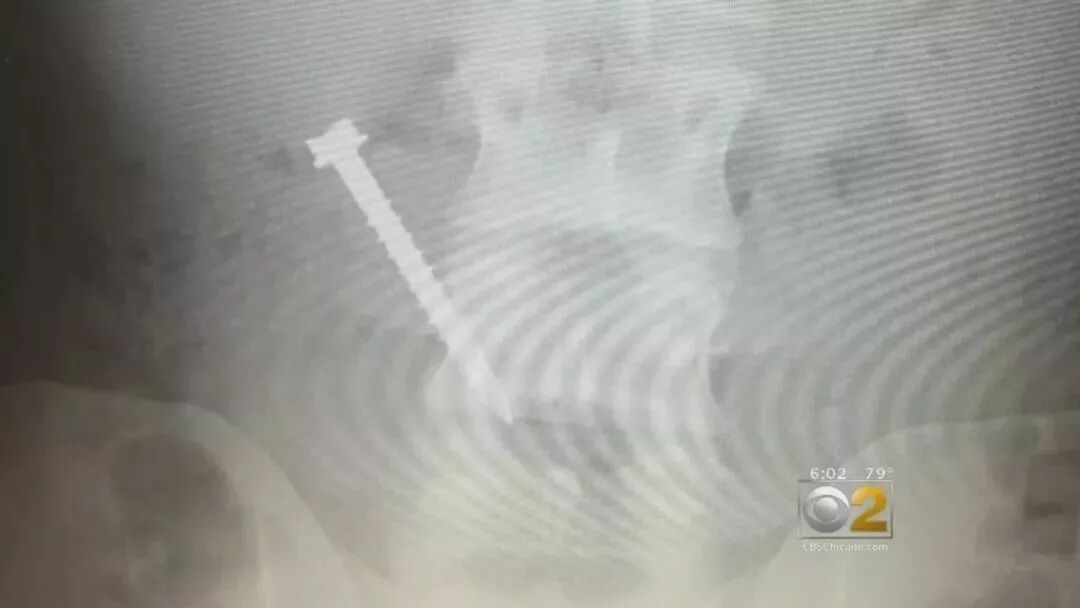

所謂的“狂吃”不是胃口大,而是看見什麼吃什麼,包括灰塵、掉落的

鐵釘、螺絲帽、垃圾桶鐵皮等不正常的東西,全都進了他的肚子。

正是因為他什麼都敢吃,導致他的胃功能經常受到損害,光是專門送他去

醫院檢查治療都有20多次,在他身上花費了近100多萬美元......